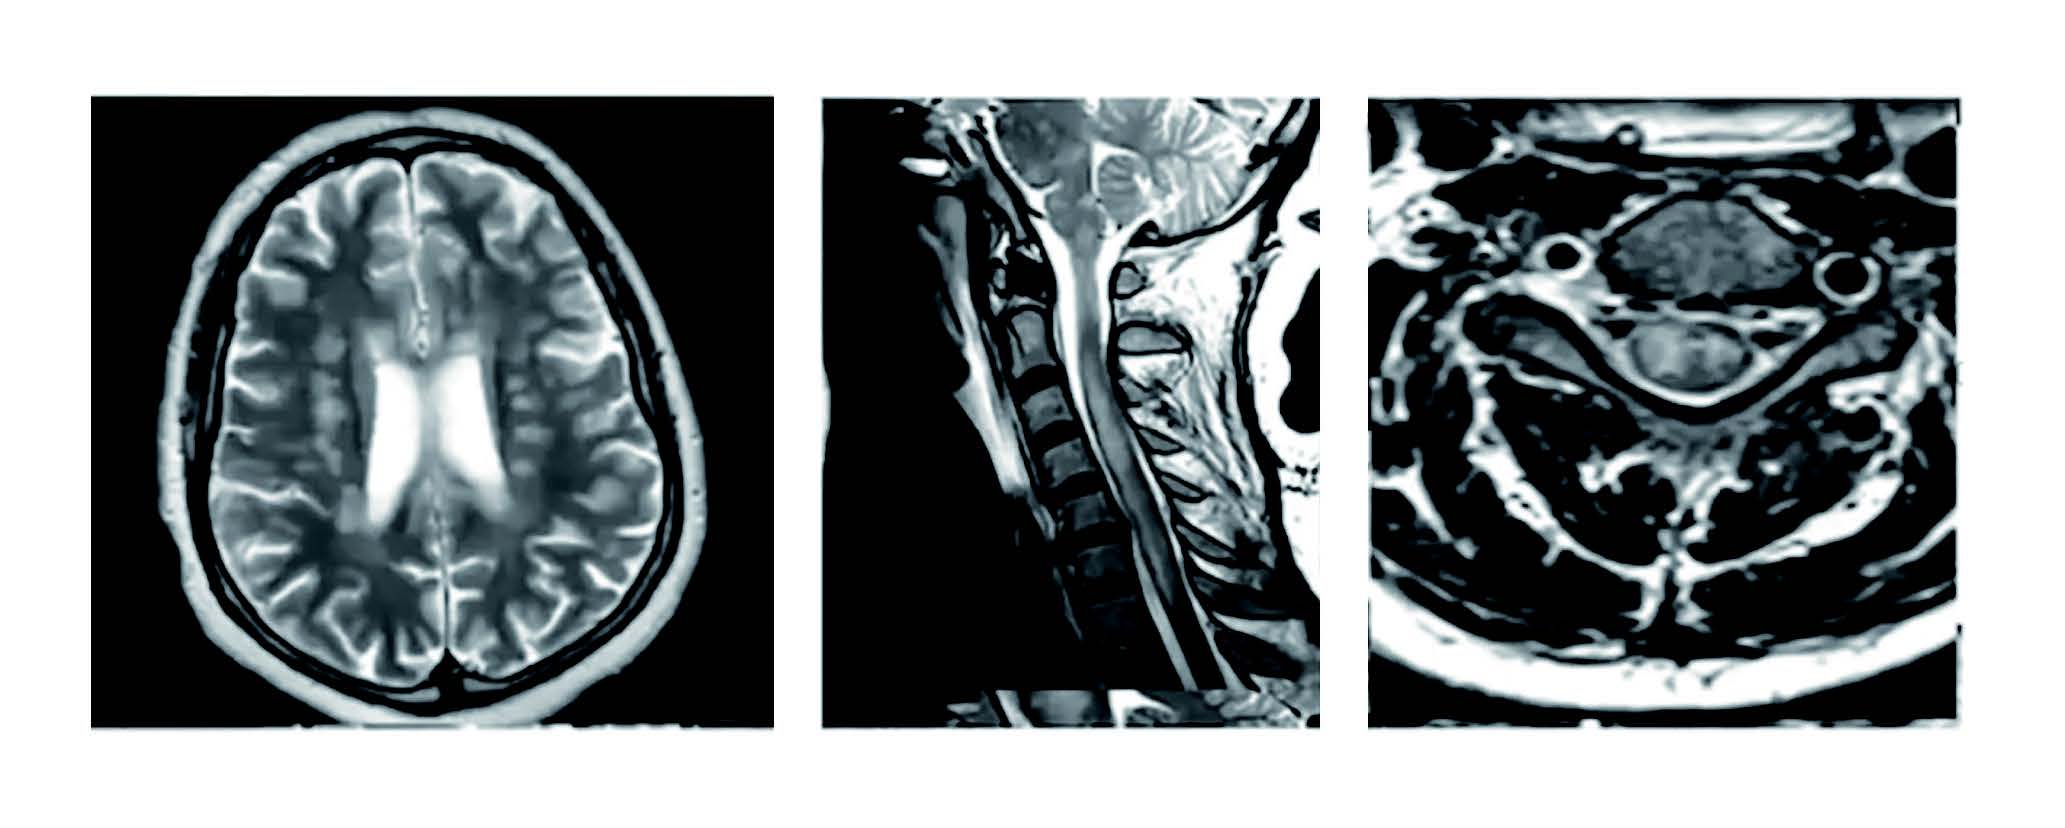

신종 코로나바이러스는 호흡기뿐만 아니라 뇌와 척수 같은 중추신경계에도 영향을 미친다. 인후통이나 콧물, 기침과 같은 호흡기 증상을 일으킬 뿐 아니라 혈관과 폐, 심장, 신장, 췌장 등 장기를 손상시키고, 더 나아가 뇌에도 침투하여 신경, 정신적 문제까지 일으킬 수 있는 것이다.

코로나바이러스가 뇌에 침투하는 방법은 세 가지다. 첫 번째는 코를 통해서 뇌로 들어가는 것이다. 코로나바이러스로 사망한 환자들에게서 바이러스가 가장 많이 발견된 곳은 후각 신경이다. 비강(콧구멍에서 목젖 윗부분에 이르는 빈 공간) 상부의 뼈에는 작은 구멍들이 있는데, 후각 신경과 미각을 담당하는 삼차 신경이 이 구멍을 통해 뇌와 연결되어 있다. 뇌는 경질막이라는 두터운 막으로 싸여서 보호되는데, 코와 연결된 이 부분이 유일하게 경질막으로 보호되지 않는다.